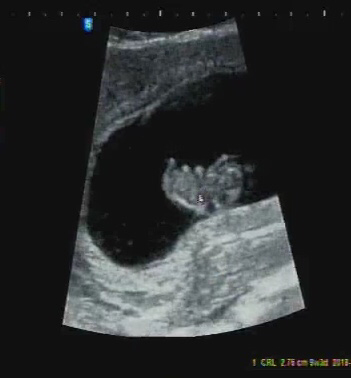

노래처럼, 미숙한 인간인 제 안에 다른 하나의 새 삶이 열릴 수 있을까 고민하며 꿈꾸던 일이 현실이 되었습니다. 하늘이 이대로 이 선물을 허락한다면 10월에는 저도 한 아이의 엄마가 돼요. 그런데 머리로는 알면서도 실제로는 전혀 실감 나지 않아 종종 잊어버리곤 해요. 아마 그래서 입덧이라는 알림을 통해 홀몸이 아님을 확인시켜주는 것일지도 모르겠네요.

매일 조금씩 그러나 쑥쑥 자라고 있는 튼튼이 :)